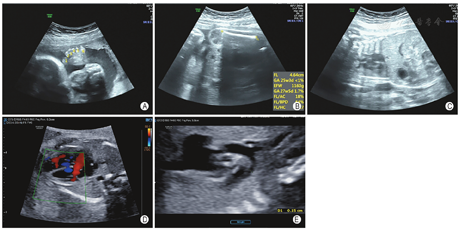

后孕妇继续妊娠随访,长骨呈进行性发育不全(表1,图1)。孕30+3周行超声检查,提示胎儿一侧股骨径46 mm(-3.99SD),一侧肱骨径39 mm(-5.28SD);胎儿腹围251 mm,胸围199 mm,呈现胸廓窄小,腹部相对膨隆;胎儿右房右室大于左房左室,主动脉弓峡部内径偏细,另见室间隔上段回声失落;另外可见胎儿双手、左足呈六指(趾)畸形(图2);其他阳性征象包括侧脑室增宽,双肾回声稍增强。超声诊断为骨发育不良,考虑短肋多指综合征可能。

经多学科综合评估,考虑为致死性骨发育不良,与孕妇沟通后,选择终止妊娠。征得孕妇及家属知情同意及伦理委员会批准后,将引产后胎儿标本进行X线成像,表现为:胸廓狭窄,短肋畸形,四肢长骨均短小,另可见多指(趾)畸形(图3)。同时,将引产后胎儿组织及双亲外周静脉血送至生殖中心实验室,检出DYNC2H1基因的c.4918(exon32)T>C/p.C1640R(NM_001080463)、c.1486-5(IVS10)T>G(NM_001080463)的复合杂合变异(图4A,图4B),寻找并对比该孕妇第一胎的基因结果,证实两胎儿携带同样的变异。其中c.1486-5T>G遗传自正常的母亲,并经RNA反转录测序验证,证明该变异影响了该基因的正常剪切,最终评级为可能致病性变异(图4C)。而c.4918(exon32)T>C遗传自正常的父亲,经多种生物信息学软件预测出变异对基因及基因产物有影响,再结合两胎儿相同的表型、基因型,在家系中共分离,最终也升级为可疑致病性变异。最终综合诊断患儿为短肋多指综合征Ⅲ型。